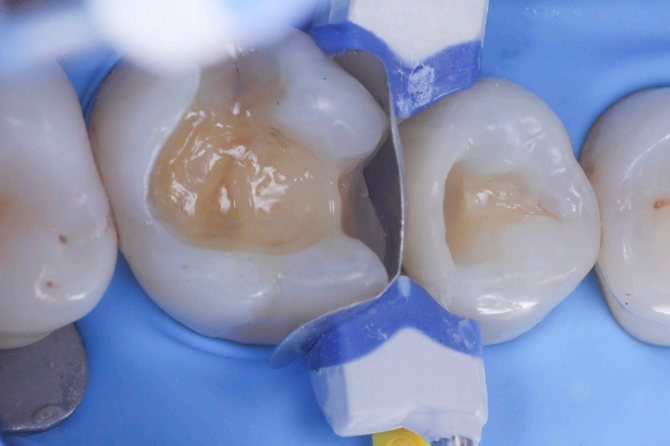

Fig.1 Fotografia inizialeFig.2 Isolamento e aspetto delle cavità ultimate

3

4

Fig.3 Aspetto vestibolare della cavità ultimateFig.4  Aspetto della chiusura cervicale e sulle pareti assiali dato dalla prima matrice